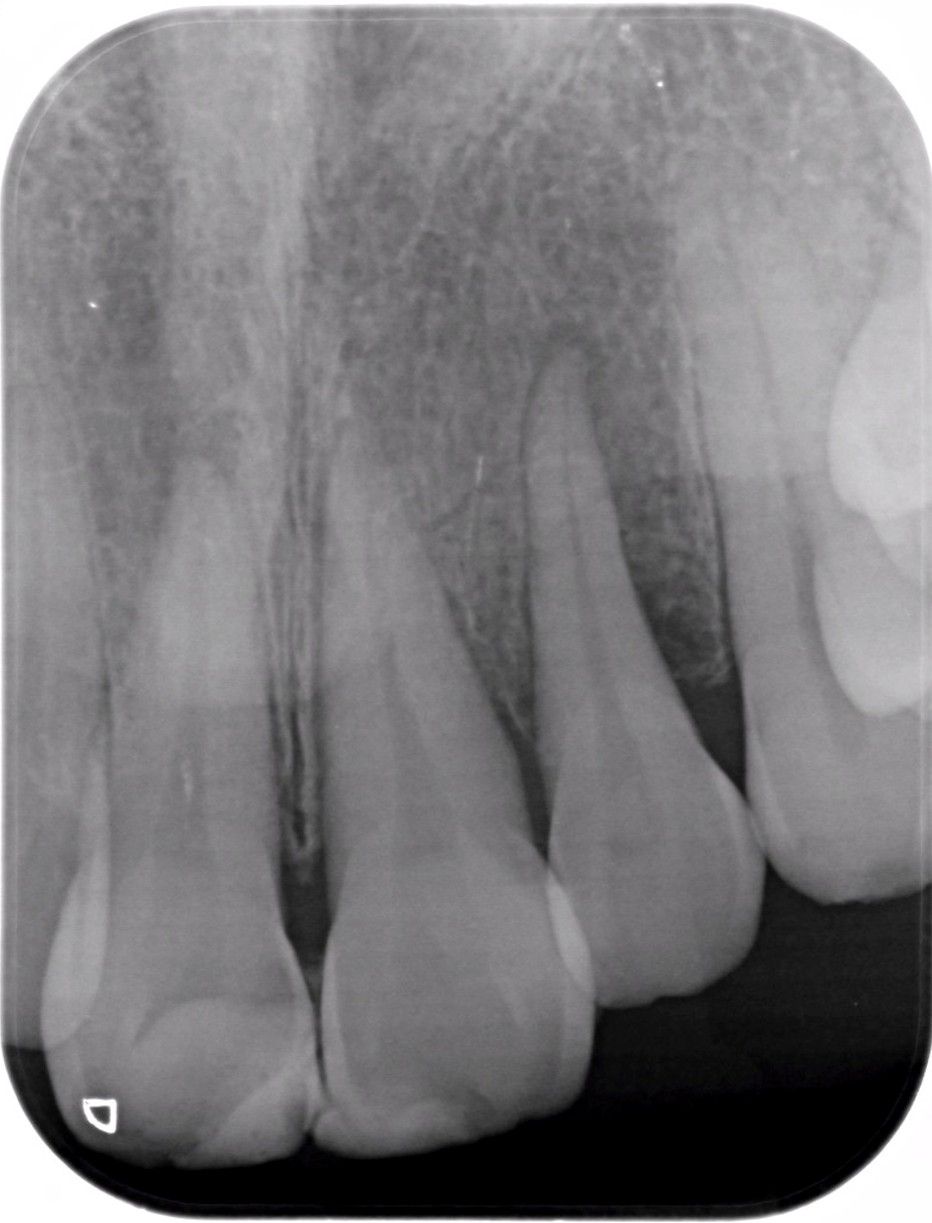

| 医院の診断 | 外傷による歯の亀裂、慢性根尖性歯周炎 |

| ここがこだわりのポイント!☝ | 外傷で歯の神経が壊死しており、変色歯になっていたので、丁寧に根管治療を行ってからセラミックにて審美性の回復を行なっています。 |